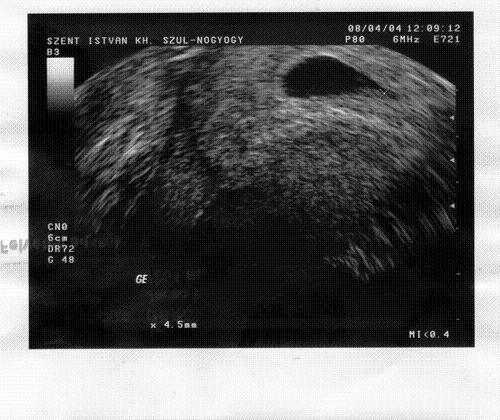

Kedden, amikor említettem a mini hőingadozásaimat, csak nem nyughattam, mert ismerős volt, csak intenzitása volt jelentősen kisebb. Be is mentem hát a klinikára. Nagyon, de tényleg nagyon rendesen megvizsgáltak. Halmos doktornő volt az egyik ügyeletes, ő vizsgált. Aggódva nézte az UH-t velem együtt, ugyanis a méhben talált valamit, ami megfeleltethető volt petezsáknak, a jobb petefészkem meg majdnem öklömnyi.

Szegény, alig akarta nekem elhinni, hogy milyen régen menstruáltam, mert a petezsákban sok mindent nem talált. Így nem engedett haza - áldom az okosságáért utólag -, mert méhen kívülire gyanakodott, de annyival bíztatott, hogy lehet, rövidebb ideije vagyok terhes, mint ahogyan azt én gondolom. Mivel barna pöttyöm is volt, hőingadozásom, és már kívántam a cigit is, én már sejtettem a bajt.

Szerda reggel vérvétel, HCG szint vizsgálat, elküldtek belgyógyászhoz is, hátha mégis méhen kívüli, és hasi műtét, de UH-t is csináltak. Az UH-n már görcsöltem, nem is volt a méhben petezsák, UH utáni törölközéskor az a kezemben maradt... A petefészek azonban az éjszaka alatt nőtt, a hőingadozás volumene is (a hormonok elkezdetek visszaállni). Másnap méhöblítés, ma megint HCG mérés, és mivel az már csak 50, így hétvégére hazaenedtek (nincs méhen kívüli). Hétfőn vissza, HCGmérés és petefészek nézegetés... Hőingadozás most is van még, ugye amíg a HCg visszaesek a bázisszintre, tartani is fog...

Petefészek problémával kapcsolatban több gyanú is van, az egyik sárgatest bevérzés, így nem termelt hormont, ami megtartotta volna a terhességet, ezért vetéltem. De hát van más verzió is, utána kell járni...